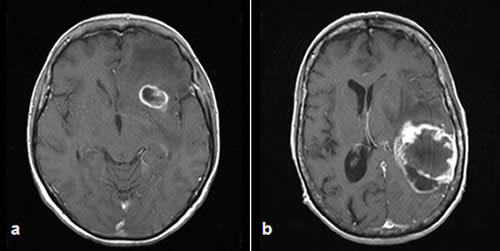

Glioblastoma en humanos

Glioblastoma es el tipo de cáncer más letal y de peor pronóstico del sistema nervioso central, según explicó la investigadora. “Es agresivo, altamente invasivo y de rápido crecimiento, lo que implica resistencia a los tratamientos existentes”, detalló.

Quien sufre de glioblastoma tiene un 40 por ciento de posibilidades de sobrevivir tras un año de padecerlo y un 5 por ciento tras cinco años, a pesar de la extracción quirúrgica del tumor, la quimioterapia y la radioterapia.